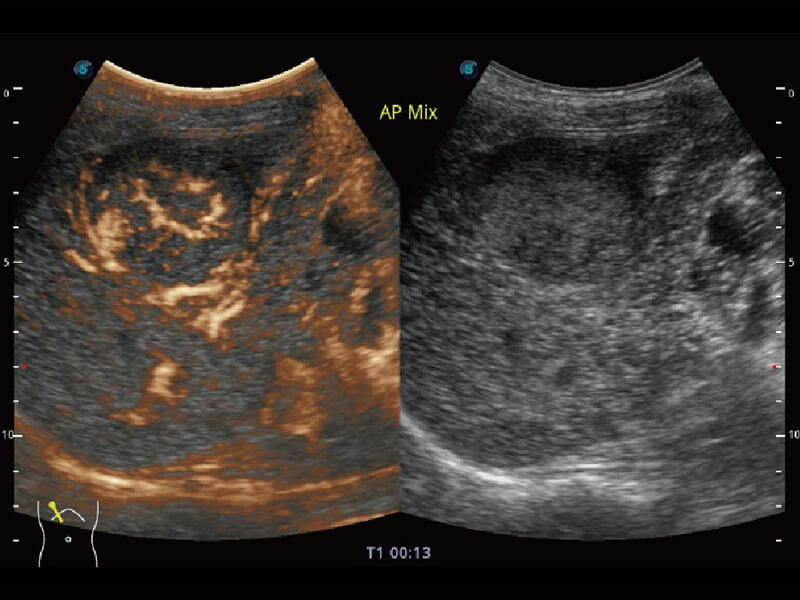

性能优异的硬件架构,极大提升超声系统的运行效率和数据处理能力。相比以往超声成像系统,Wis+平台为您带来极快的响应速度和成像帧频,提升检查流畅度。